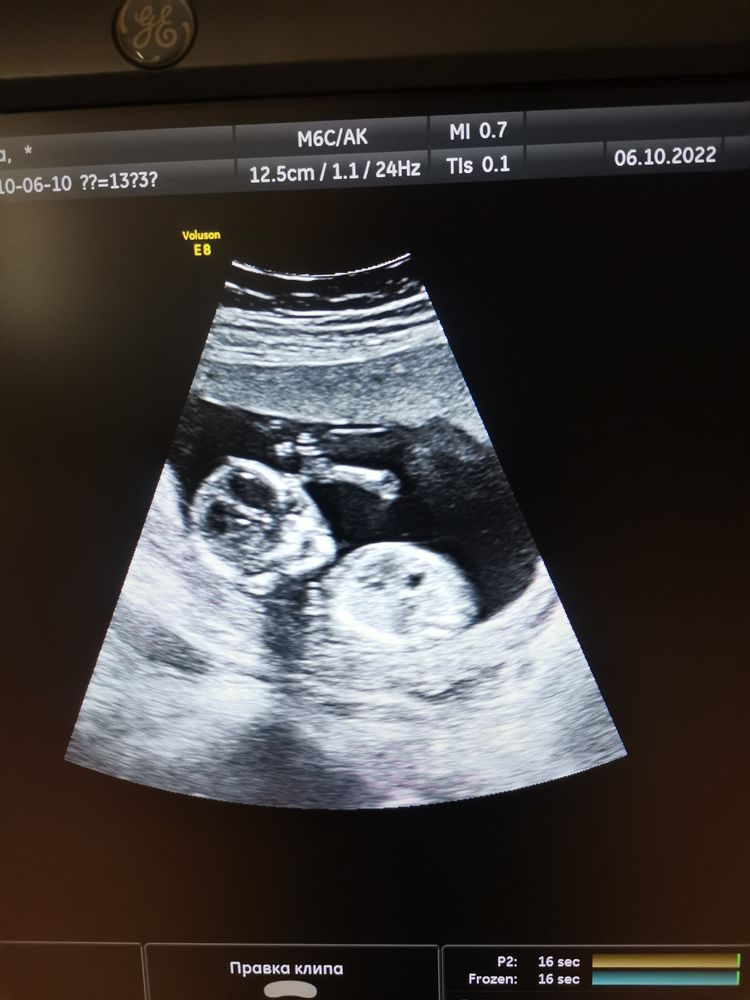

Первый скрининг пройден 🥳

Немного было волнительно, но.. выдыхаю. Показатели все в пределах нормы. Осталось дождаться результатов крови. Мне казалось по ощущениям, что будет мальчик🥰 и что же нам говорят: "у вас мальчишка" 🥳🥳🥳(надеюсь не ошиблись)). Ручки, ножки, всё такое родное 💕